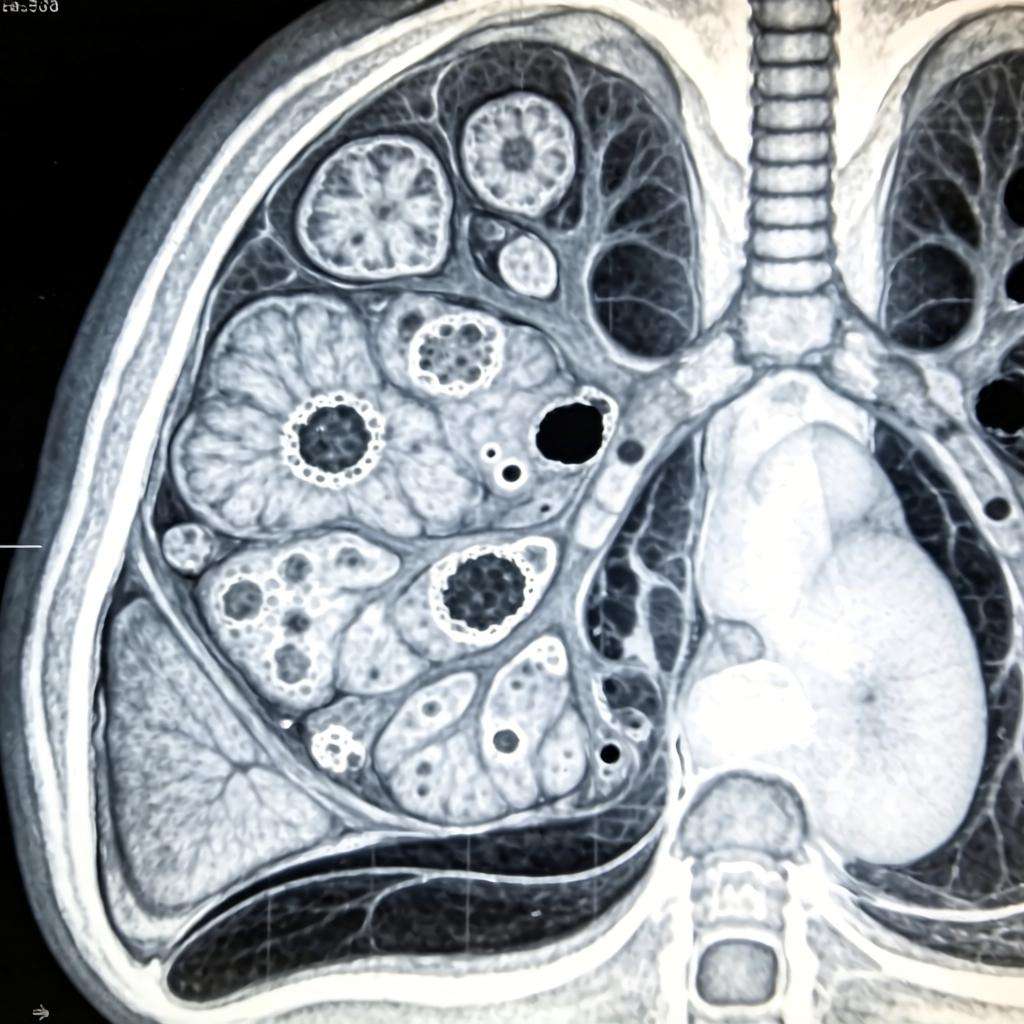

从需求端来说,中国年新增肺癌患者数量全球第一,年肺癌因素死亡人数全球第一,早筛需求旺盛,低剂量螺旋CT正被广泛推广;而从图像质量上来说,胸部CT图像分层薄、视野清晰、干扰因素少、病灶特征规律可循,是智能影像判读的理想用武之地,加之中国影像医师的稀缺及国家政策的大力推动,这一领域的应用基础堪称完美。

2017年,主攻肺结节检出的各大AI企业都交出了辉煌的答卷,敏感性一路飙升,95%、96.5%、98.8%……人类肉眼难以察觉的像素差别,在AI强大的算力面前无所遁形。

目前临床上为了确保影像判读的准确性,通常由一名执业医师与副主任医师共同阅读同一个患者的胸片,影像医师在读片完毕之后,还需要上级医生复查一遍,签字确认。AI的目的正是替代这个步骤中的第一环节,因为AI医生不仅“视力”极好,几乎可以看出每一个微小结节,同时,AI医生不知疲倦,不会出现视觉疲劳,看成千上万张胸部CT也不过毫秒之间。

将AI的灵敏度不断提升,理论上AI可以发现肺部的每一个结节,但是随之而来的误报率却令人头痛,是迅速将敏感性提升到极致,暂时忽略误报率?还是花费更大的力气,将敏感性与误报率同时提升到可用水平?亦或是还有更加科学准确的考核指标?

国内著名放射学家、浙江省人民医院放射科主任龚向阳教授曾表示,特异性和敏感性兼顾起来是很难的,所以很多公司在开发系统时会优先考虑敏感性的问题,在保证敏感性的前提下,提高特异性。

“敏感性与误报率确实很难兼得,极其考验AI企业的技术功底,既要保持足够的敏感性,但又要确保足够低的误报率,确保找出来的结节绝大部分是正确的,是有临床意义的,并没有外界看起来那么容易难度,依图医疗付出了艰苦的努力,在这两方面都做到了业内领先水平”,依图医疗总裁倪浩在接受媒体采访时表示,“误报一旦过高,将极大增加医生的工作压力,也丧失了AI助力临床的初衷。”